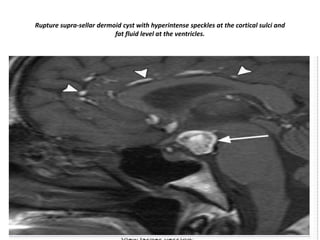

Rupture supra-sellar dermoid cyst with hyperintense speckles at the cortical sulci and

fat fluid level at the ventricles.

Rupture supra-sellar dermoidcyst with hyperintense speckles at the cortical sulci and fat fluid level at the ventricles.